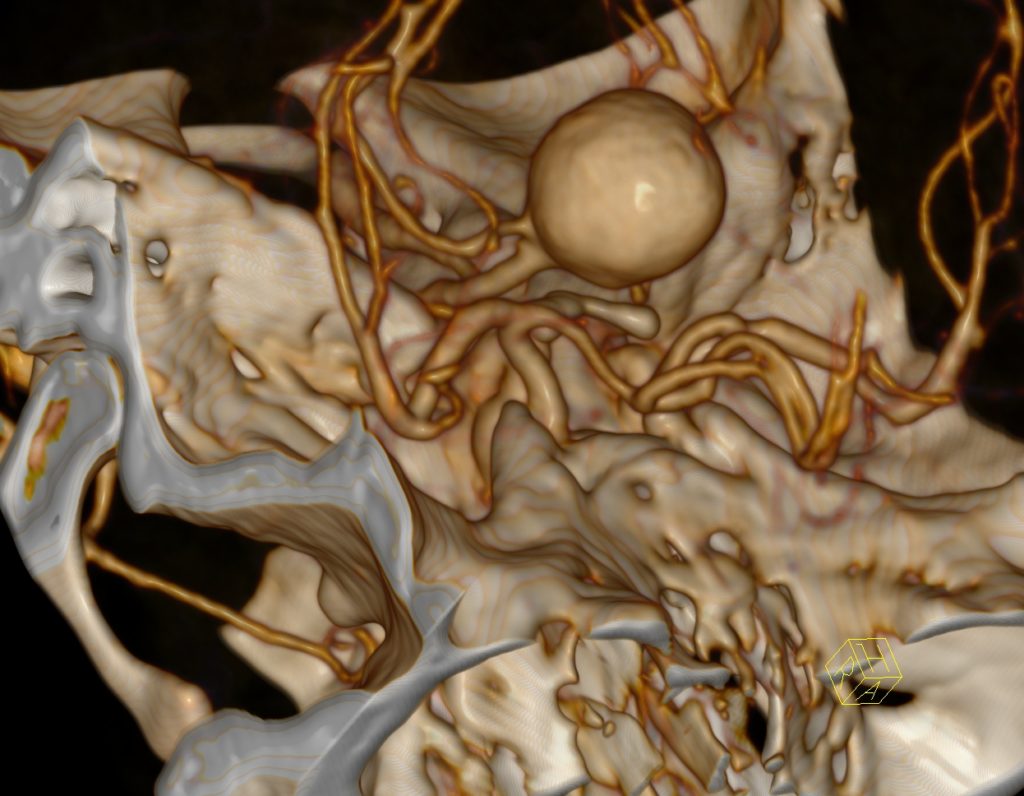

- caracterizarea anevrismelor, stenozelor și anomaliilor vasculare;

- planificarea tratamentului intervențional.exclude cauzele care mimează AVC;

- indică prezența ocluziei, gradul și localizarea acesteia;

- precizează extensia trombului (poate fi cuantificată prin măsurarea lungimii acestuia în arborele arterial. Extinderea intracranială a trombului prezice evoluția clinică, mărimea finală a infarctului și transformarea hemoragică)